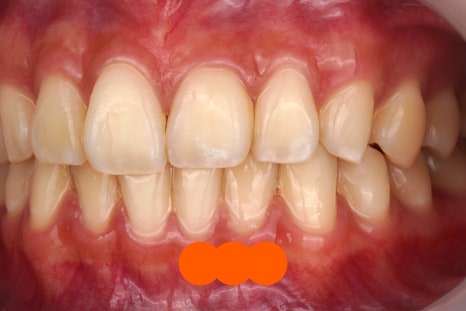

제거 전

제거 후

진짜 깨끗하게 떨어졌죠

그냥 뗀 게 아니라

치과용 기구를 이용해서 정확히 떼어내고

전문적인 앞니 치료 도구들을 활용해서

치아 표면을 활택하게 만듭니다.

어디에 접착제가 묻어있었고

어디에 투스젬이 있었는지

정말 감쪽같이 떨어지지 않았나요?